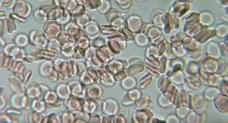

Aufhebung von Geldrollenbildung im Blut

Aufhebung von Geldrollenbildung im Blut

Aufhebung von Geldrollenbildung im Blut